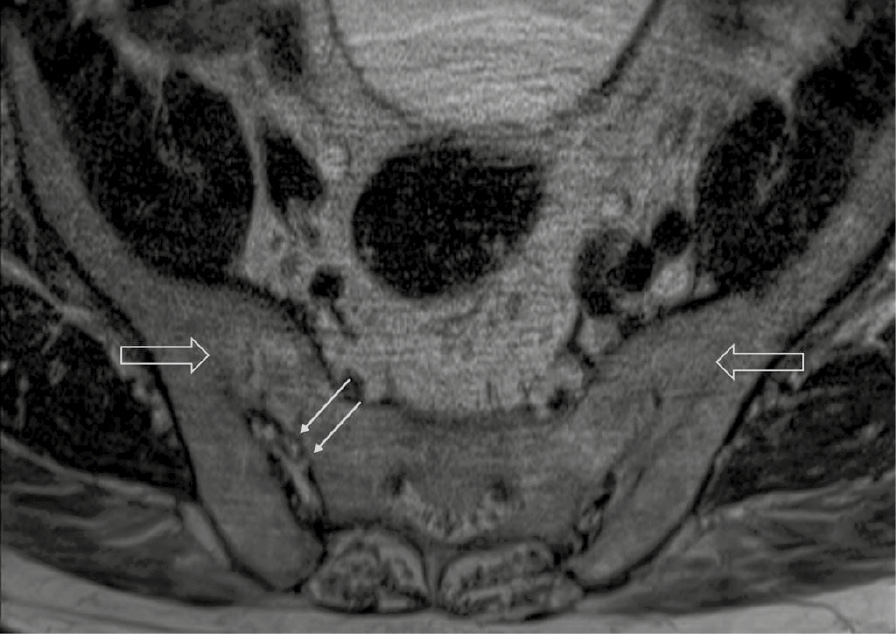

При компьютерной томографии органов грудной клетки данных за «свежие» очаговые и инфильтративные изменения не получено. Увеличения лимфатических узлов подмышечных областей, средостения, корней легких не выявлено. Отмечался усиленный грудной кифоз, обызвествление передней продольной связки, на всем уровне исследования определялись передне-боковые спондилофиты, а также анкилоз большинства реберно-поперечных суставов. По данным рентгенографии кистей (рис. 1, 2) и стоп (рис. 3, 4) диагностированы признаки эрозивного артрита, анкилоз суставов запястья. По данным МРТ крестцово-подвздошных суставов (КПС) определялся неравномерный анкилоз КПС, хрящи по суставным поверхностям неравномерной толщины, примерно на половине протяжении сустава отсутствуют, «суставной промежуток» облитерирован. Неравномерность и нечеткость контура суставных поверхностей за счет множества краевых эрозий справа, единичных – слева, с наличием остеокластоза, в нижнем отделе слева по смежным отделам определяются участки трабекулярного отека, данная находка клинически интерпретирована как двусторонний активный сакроилиит (рис. 5, 6).

Рис. 5. Магнитно-резонансная томография (Т2-взвешенное изображение в поперечной проекции). Протяженные участки анкилоза крестцово-подвздошных сочленений (толстые стрелки), эрозии суставных поверхностей (тонкие стрелки)

Рис. 6. Магнитно-резонансная томография (Т1-взвешенное изображение в косой корональной проекции). Протяженные участки анкилоза крестцово-подвздошных суставов (толстые стрелки), субхондральная киста правой латеральной массы крестца (тонкая стрелка). При магнитно-резонансной томографии крестцово-подвздошных сочленений с обеих сторон определяются крупные зоны анкилоза (суставные щели полностью облитерированы на 1/3 поверхности сустава справа, на 2/3 поверхности слева, что соответствует III рентгенологической стадии сакроилиита справа, IV стадии слева по Келлгрену). На остальных участках суставной хрящ неравномерно истончен, суставные поверхности неровные за счет множественных эрозий справа, единичных – слева. Определяются единичные мелкие (4 мм) субхондральные кисты справа

Ведущим диагнозом в течение всей истории заболевания был «анкилозирующий спондилоартрит, смешанная форма, HLA-B27-ассоциированный», поставленный на основании типичного поражения позвоночника с формированием деформаций (костный анкилоз в переднем отделе Th4 и Th7, множественные синдесмофиты в области передних углов тел позвонков). Заключение МРТ КПС типично для пациента с АС: двусторонний анкилоз КПС, множественные краевые эрозии, с наличием остеокластоза и признаками трабекулярного отека костной ткани, двусторонний сакроилиит. Клиническая картина, проявляющаяся болями воспалительного характера и скованностью в пояснично-крестцовом отделе позвоночника, нарушением объема движения в позвоночнике, была характерна для прогрессирования АС. Диагноз подтверждался наличием положительного гена HLA-B27 [2].